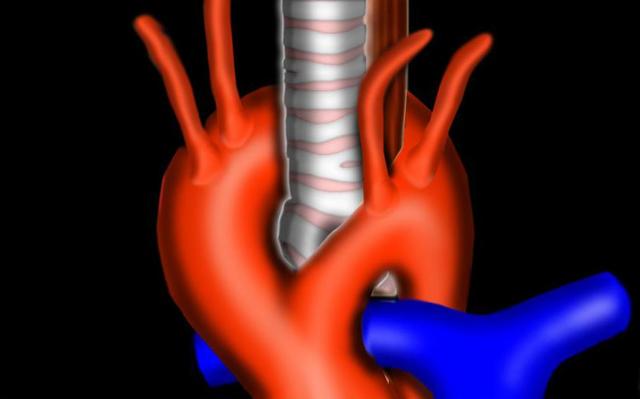

Аорта условно подразделяется на три отдела: восходящий, начало которого лежит у сердца, дуговой и нисходящий (нижняя часть). Нисходящий делится на брюшной и грудной отдел.

Верхняя ее часть отходит от левого желудочка миокарда на уровне третьего ребра. Затем она расширяется в устье, образовывая сфероподобную луковицу. В этой области находится клапан и три синуса Вальсальвы — выпуклые стенки луковицы.

От начала луковицы отходят две ветви — правая и левая венечные артерии. Они вместе с соответствующими венами образуют сердечный круг кровообращения. Далее восходящий отдел поднимается вверх и, сужаясь, переходит в дугу (изгиб) аорты. Затем дуга опускается назад и влево. Здесь образуется нисходящий отдел, отделяемый от дуги небольшим перешейком.

От верхнего изгиба дуги отходят три крупных сосуда — плечеголовной ствол, общая сонная и подключичная артерии. К ним присоединяются артерии легких, вены и артериальные связки.

Нижний отдел аорты имеет самую большую длину. На уровне четвертого поясничного позвонка он разделяется на подвздошные артерии (левую и правую).

Грудной отдел этого сосуда располагается в грудине, в левой стороне от пищевода. На уровне 8 грудного позвонка эта часть аорты отгибается назад и возле 12 позвонка переходит в брюшную.

Брюшной отдел отводит артериальные ветви к диафрагме и заканчивается тонкой крестцовой артерией.